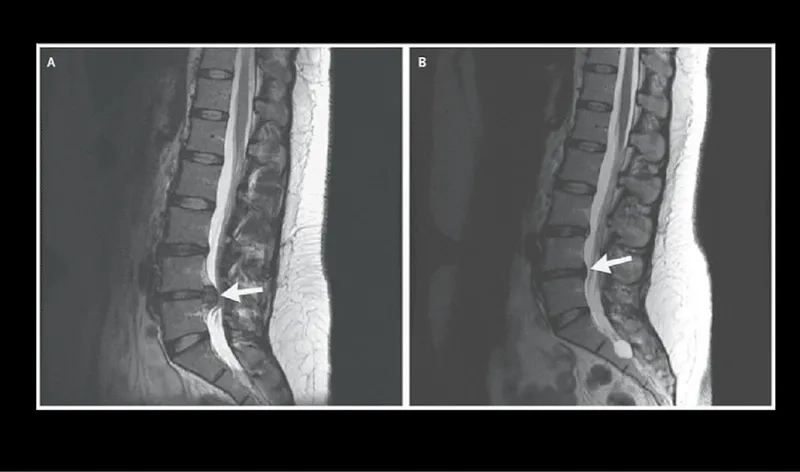

An MRI showing a lumbar herniated disc